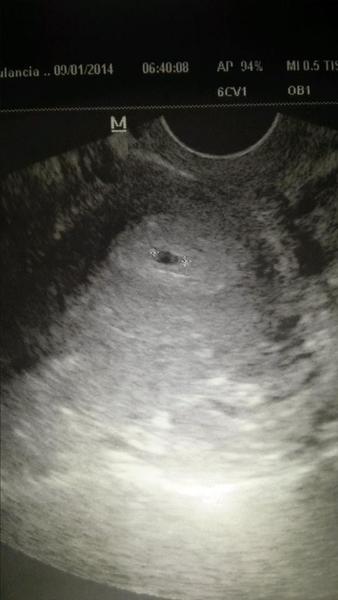

@jana21278 Ahojte babenky 🙂 tak mame malu bublinku.videli sme len gestacny vacok nebolo este babatko ani srdiecko. gestacny vacok mal 5,8 mm tak dufam ze neni malicky ze je akurat ako ma byt 🙂 🙂 robili mi aj kontrolne HCG a z 279 nam stuplo na 3900 😀 😀 😀 tu pridavam fotecku nasej bublinky. 22.1 mame dalsiu kontrolu vraj by malo byt vidno aj srdiecko 🙂